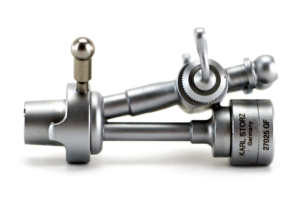

Obturador

Asa de corte y coagulación

Elemento de trabajo

- Corte mediante tensión de resorte.

- Anilla móvil para pulgar.

- Por seguridad, en posición de reposo, la punta del electrodo se encuentra dentro de la vaina.

Vaina de resectoscopio

- Vaina de resectoscopio de 26 Fr.

- Vaina interior con aislamiento de cerámica.

Cable de alta frecuencia o activo

Obturador

Asa de corte y coagulación

Elemento de trabajo

- Corte mediante tensión de resorte.

- Anilla móvil para pulgar.

- Por seguridad, en posición de reposo, la punta del electrodo se encuentra dentro de la vaina.

Vaina de resectoscopio

- Vaina de resectoscopio de 26 Fr.

- Vaina interior con aislamiento de cerámica.

Cable de alta frecuencia o activo

Llave de paso